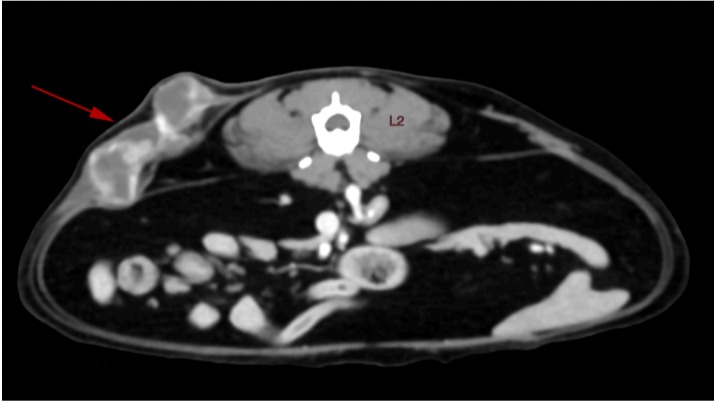

She suffered from FIP (feline infective peritonitis) three years ago and thanks to all of you who donated, she's alive today. Unfortunately, the treatment for FIP was only through injections back then. These injections caused an inflammatory reaction in Leia's skin which induced the development of the mesenchymal tumor she has today.

I found two small bumps on her skin a week and a half ago while giving her pets, so I took her straight to the vet. After a biopsy and CT scan, we now know we need to move as fast as possible to operate and give her radiotherapy to obtain the best possible outcome.